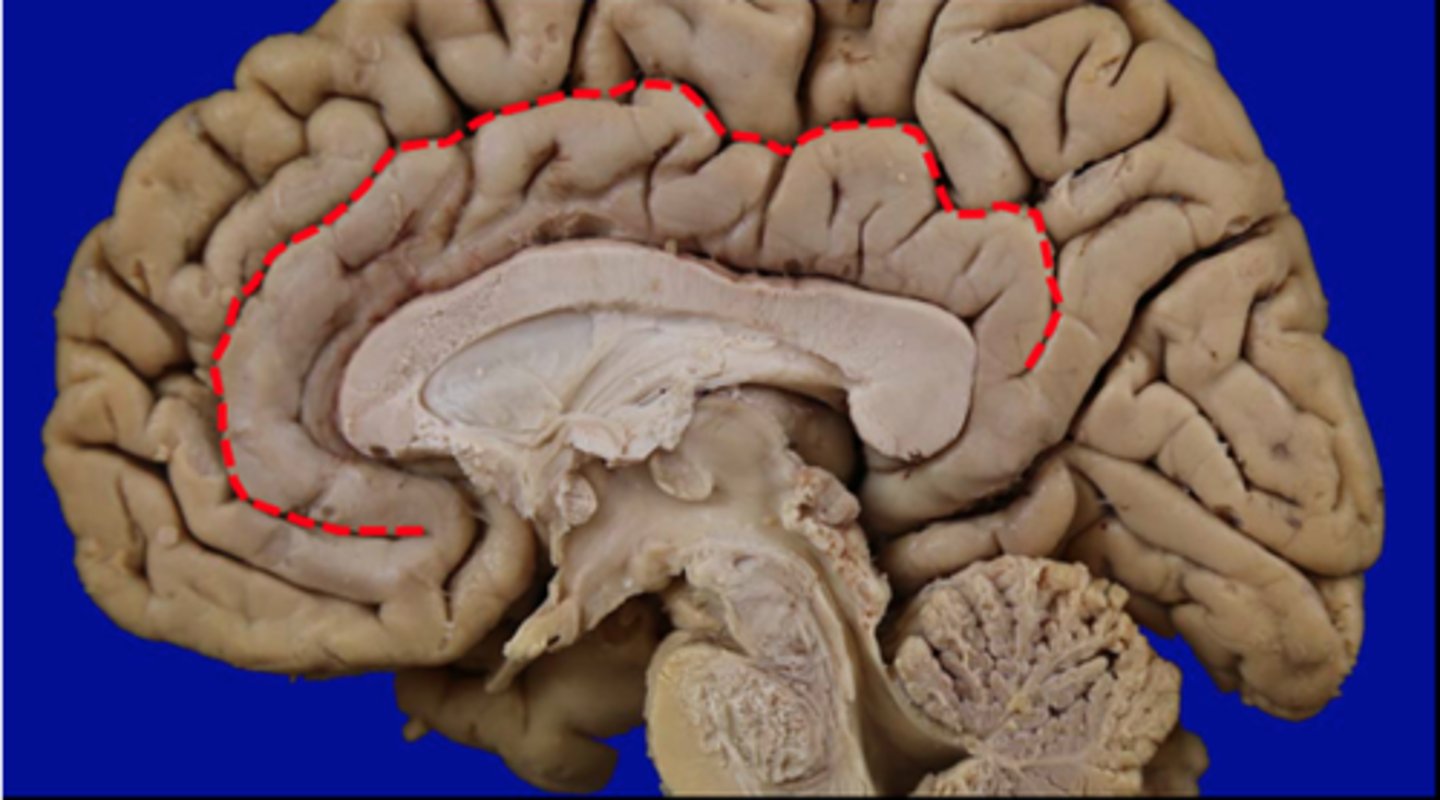

Cingulate gyrus

ridge, bigger sombrero

Cingulate sulcus

depression

Corpus callosum

structure, first sombrero